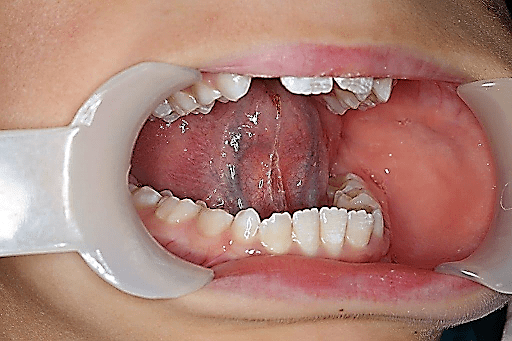

Test for frenum surgery

High lingual Frenum